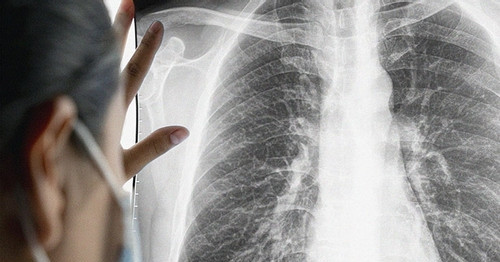

Qua chụp MRI sọ não, bác sĩ phát hiện bệnh nhân có nhiều ổ tổn thương di căn dạng biểu mô tuyến. Nghi ngờ di căn từ phổi hoặc đại tràng, bà được chụp CT phổi và phát hiện khối u ung thư phổi lớn ở đáy phổi trái. Đáng tiếc, ung thư đã di căn lên não, cột sống và xương chậu, tiên lượng xấu.

Ung thư phổi hiện là một trong những bệnh ung thư hàng đầu ở nam giới và ngày càng gia tăng ở nữ giới. Theo GS.TS Mai Trọng Khoa, nguyên Giám đốc Trung tâm Y học hạt nhân và Ung bướu, Bệnh viện Bạch Mai (Hà Nội), tại Việt Nam và trên thế giới, tỷ lệ mắc ung thư phổi đang tăng đáng báo động. Một trong những nguyên nhân chính, đặc biệt ở nữ giới, là hút thuốc lá thụ động.

Giáo sư Khoa lo ngại về tỷ lệ thanh thiếu niên sử dụng thuốc lá và thuốc lá mới (như thuốc lá điện tử) vẫn ở mức cao, làm gia tăng nguy cơ ung thư phổi trong tương lai. Ông khuyến nghị tầm soát sớm cho những người có nguy cơ cao, như người hút thuốc chủ động hoặc thụ động. Chụp CT liều thấp có thể phát hiện tổn thương nhỏ, trong khi các kỹ thuật hiện đại như PET/CT, PET/MRI, kết hợp sinh học phân tử, giúp xác định đột biến gene và lựa chọn điều trị trúng đích hiệu quả.